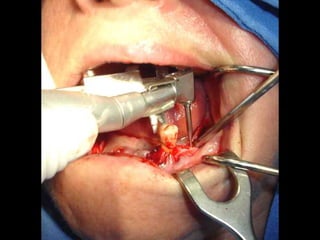

Plastia de maxilares para implantes dentales.

Plastia alveolar con factores de crecimiento y

traspalnate de hueso cadaverico

La conformación quirúrgica de un contorno alveolar adecuado es

determinante para la correcta aplicación y aceptación de los implantes

de titanio, aquí proponemos una técinica para lograr el espesor óseo

suficiente y la corrección estética del proceso, ya que antiguamente al

extraer un diente se acostumbraba presionar las tablas alveolares

“para cohibir la hemorragia”, con el colapso subsiguiente de la región.

Incisión

Disección cuidadosa del colgajo

Defecto óseo a corregir

Múltiples perforaciones en hueso compacto

Aspecto de hueso cribado